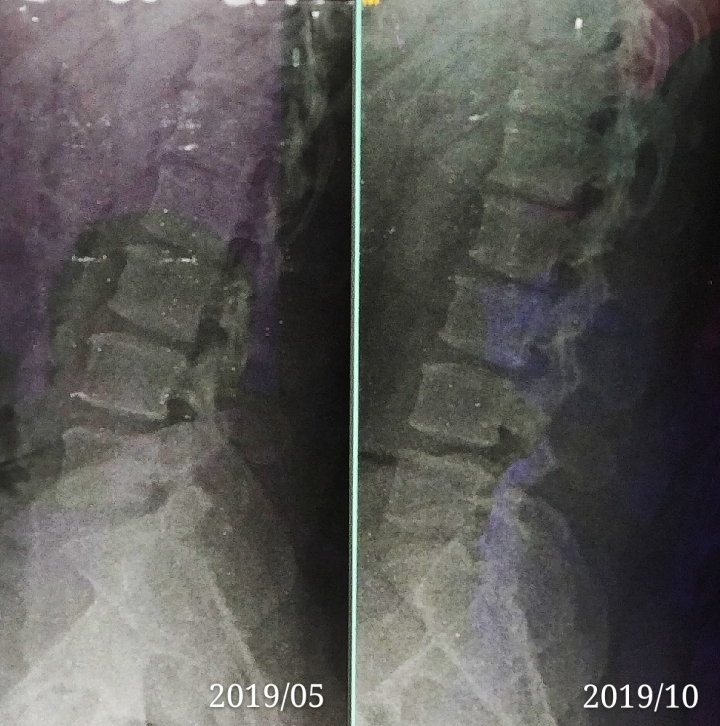

小弟前幾年的工作常會搬重物,所以偶爾感到腰痠~在去年的時候接觸到健身房就想說靠健身提升身體素質應該身體就會正常很多~大概今年就開始覺得腰的酸痛次數好像開始有點頻繁~四月多的時候就突然痛的很厲害,甚至只要站著不... 更多